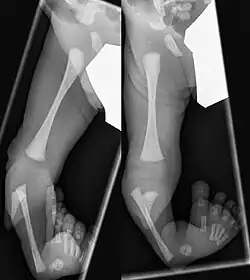

Eine Tibiale Hemimelie oder ein Tibialer Längsdefekt bezeichnet das angeborene Fehlen (Aplasie) oder die Unterentwicklung (Hypoplasie) der Tibia. Sie kann isoliert, häufiger aber in Verbindung mit Fehlbildungen am Fuß medial sowie einer Varusstellung im Rückfuß einhergehen.[1]

Bei etwa 30 % tritt die Hemimelie beidseitig auf.[2] Nur bei 50 % ist der Fuß normal angelegt, meist fehlen mediale Strahlen des Fußes, Knochenkerne des Rückfußes sind fusioniert (Sprungbein#Fehlanlagen)[7]

Bereits im Mutterleib kann während einer Ultraschalluntersuchung die Fehlbildung erkannt werden,[2] die Verkürzung und Fehlstellung des Unterschenkels ist nach der Geburt offensichtlich. Ein Röntgenbild kann das Ausmaß der Fehlbildung sowie zusätzliche knöcherne Veränderungen dokumentieren. Mittels Sonographie können die knorpeligen Anlagen und deren Stellung zum Gelenk sicher dargestellt werden, wesentlich bei den Typen II und III.